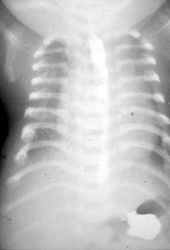

Die asphyxierende Thoraxdysplasie (Jeune-Syndrom) wurde 1954 erstmals von Jeune et al. beschrieben. Es handelt sich um ein autosomal-rezessiv vererbtes Fehlbildungssyndrom ausgelöst durch Fehlanlage des Chromosoms 15q13. Die Symptome bestehen in einem schmalen langen Thorax, kurzen Rippen, einer ausgeprägten Hypoplasie der Lunge mit schwerer Asphyxie (Abb. 1). Weitere Bestandteile sind ein Kleinwuchs, kurze Extremitäten sowie in vielen Fällen eine Niereninsuffizienz durch Nephronophthise, fibrozystische Veränderungen an Leber und Pankreas, eine Retinopathie sowie eine Hyperbilirubinämie. Die Mortalität ist bei Ausprägung aller Symptome sehr hoch. Als operative Verfahren sind die mediane Sternotomie mit Interposition einer Methylmethacrylat-prothese nach Todd sowie die laterale Thoraxexpansion nach Davis beschrieben.